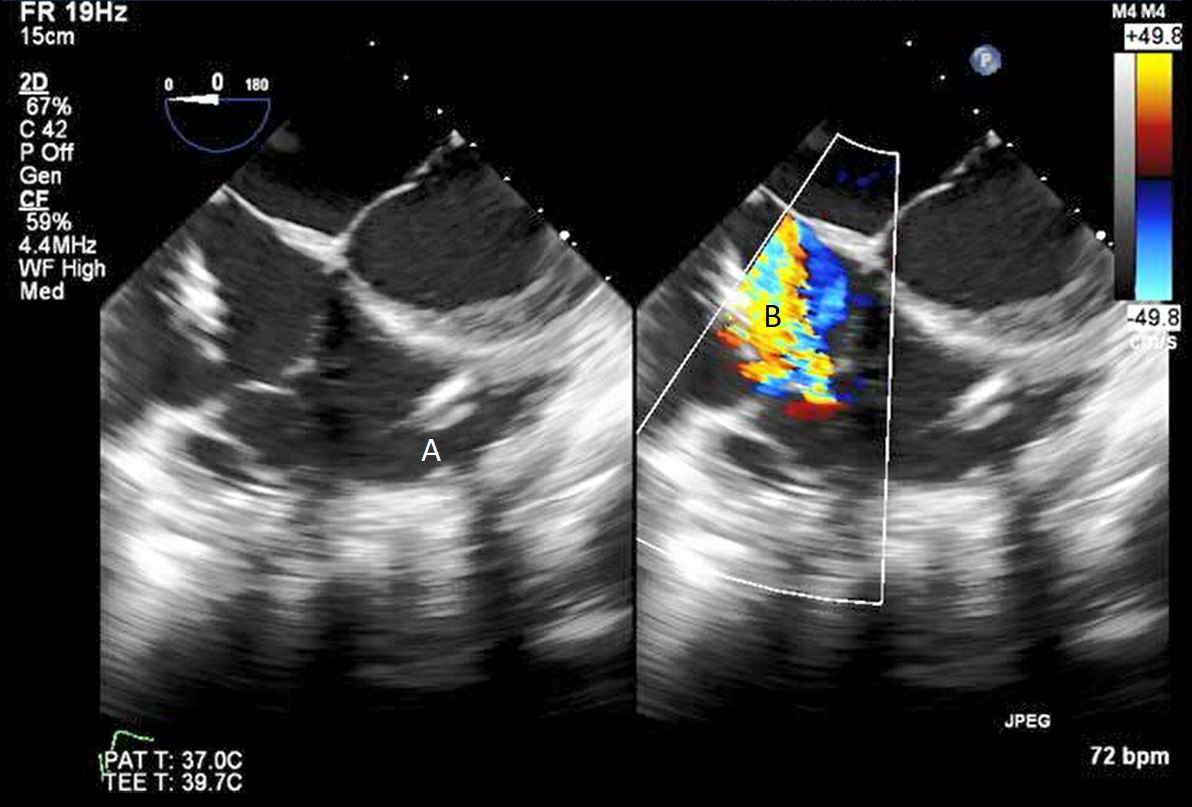

Impella (A) in the LV cavity caused disruption and damage to subvalvular apparatus resulting in flail segment (B) of the mitral valve.

Fig. 4.Impella (A) placement causing disruption and damage to subvalvular apparatus resulting in mitral valve flail (B) and mitral regurgitation (C).

After initial access is obtained with a guidewire, TEE can confirm placement of the guidewire within the aorta and ensure there is no iatrogenic dissection from the procedure. The midesophageal long axis and 4 chamber views can be used to visualize the guidewire crossing of the aortic valve and positioning within the LV cavity. The wire tip should point towards the LV apex. Wire placement too deep within the LV can trigger ventricular arrhythmias and tethering of the mitral valve or subvalvular apparatus should be avoided as this can result in the inlet abutting the mitral valve or damage to subvalvular apparatus (Figs. 3,4) [13]. When the proceduralist is advancing the Impella over the guidewire, the best view to observe the device crossing the aortic valve is the midesophageal long axis view [13].